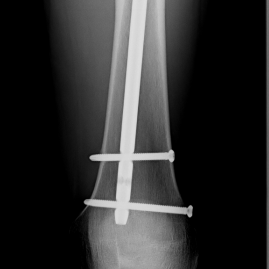

Röntgenbilder